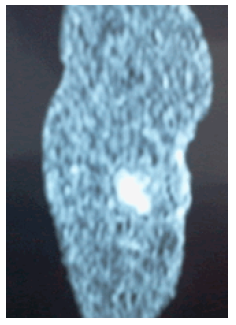

La paciente fue sometida a una intervención quirúrgica para exéresis del nódulo sin etiología clara; al realizar resección radical de dicho nódulo con anestesia regional, se obtuvo una pieza quirúrgica de 5x4x11 cm, con losange de piel de 4x1.5cm (Figuras 4 y 5).

En la Figura 4 se evidencia fragmento de tejido de 5x4x11cm con losange de piel de 4x1.5cm y superficie irregular compuesta por tejido adiposo; al corte a 0.8cm la piel presenta formación nodular de color pardo amarillento de 1.5x1.8cm con formación quística de 0.6cm de diámetro bien delimitado por tejido fibroso. También se evidencian tres formaciones quísticas de 0.3-0.8cm a 4 y 8cm debajo de la piel y paredes de 0.1cm de espesor con contenido seroso; se incluyen seis cortes.